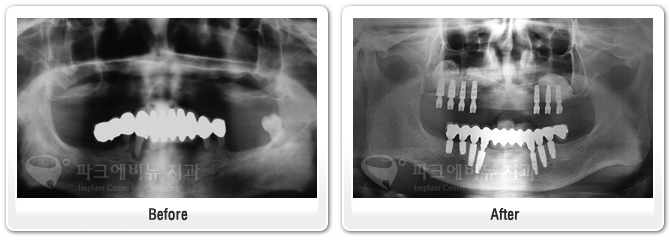

상악동거상술 이식술 뼈이식수술 치료전후 비교사진

상악동거상술

이 환자분은 위아래 틀니를 사용하시는 분인데 틀니를 거는 지대치인 앞니가 많이 흔들린다며 내원하셨습니다. 구강 내를 살펴보니 구강위생이 좋지 않아 치태,치석도 많고 잇몸이 많이 부어 있었습니다. 파노라마 방사선 사진도 살펴보면 치아를 잡는 치조골이 치아 뿌리 끝까지 많이 녹았음 확인할 수 있었습니다. 따라서 치아를 발치하고 전악 임플란트를 수복하기로 결정 하였습니다.   치료 중…